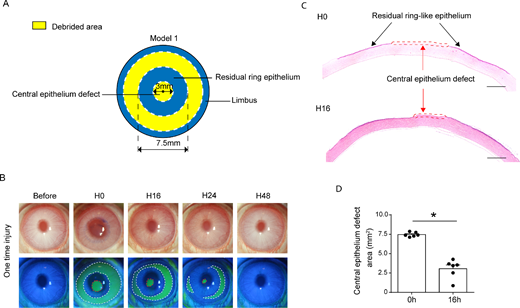

#NEIfunded research from Johns Hopkins Medicine about #AMD biomarkers: Levels of angiopoietin-like 4 and VEGF protein in eye fluid may predict likelihood of developing wet age-related macular degeneration. JCI insight: bit.ly/3OTOfYP